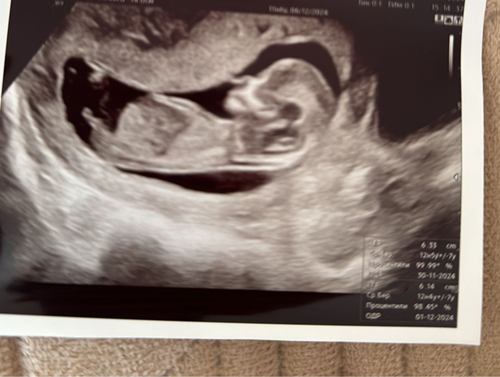

Met jouwn echo gok ik dat het een jongen in wording is. In wording omdat alles nog niet volledig op de plaats zit en dus in ontwikkeling zit. Waarom gok ik jongen?

Onderste foto is de nub van dichtbij.

Groen: de omranding van de kleine

Rood: de blaas

Blauw: de stand van nub en blaas in vergelijking met de ruggengraad

(📐) staat het in een hoek van de ruggengraad wijst het op een jongen.

(=) staat het gelijk of bijna gelijk aan de ruggengraad wijst het op een meisje.

Daarnaast is een bolletje boven de nub wat je bij jouwn echo hebt het deel wat langzaam de pipi word terwijl de lijn eronder langzaam veranderd in de balletjes. Bij meisjes zie je geen bolletje erboven daar is de nub een lijn. De blaas zal als het goed is nog iets verder zakken. Maar dat komt door het termijn waarin je zit dat het nog niet allemaal op de plek zit.